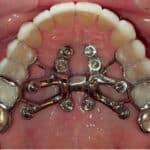

Interproximal reduction is a staple of orthodontic treatment, but traditional tools can be inconsistent. A new cylindrical IPR bur system is designed to deliver more precise, efficient enamel reduction aligned with aligner protocols.